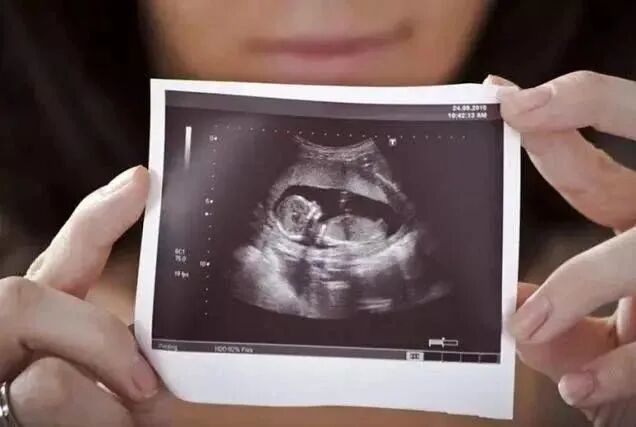

整个孕期中,B超都是一项很重要的检查

不仅因为它能监测宝宝的发育和健康状况

更因为这项检查颇具神秘色彩

能透过你的肚皮

看到宝宝的模样和动作